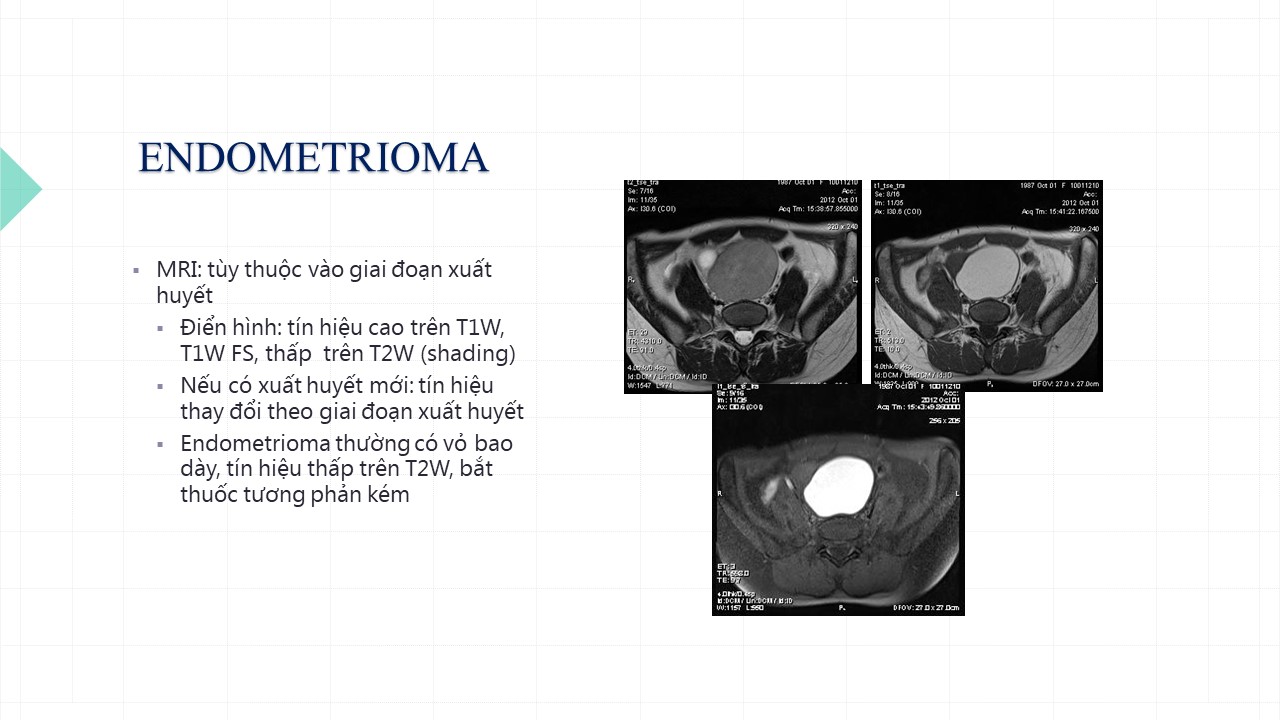

Vai trò cộng hưởng từ trong đánh giá lạc nội mạc tử cung

Từ khóa: Vai trò cộng hưởng từ trong đánh giá lạc nội mạc tử cung